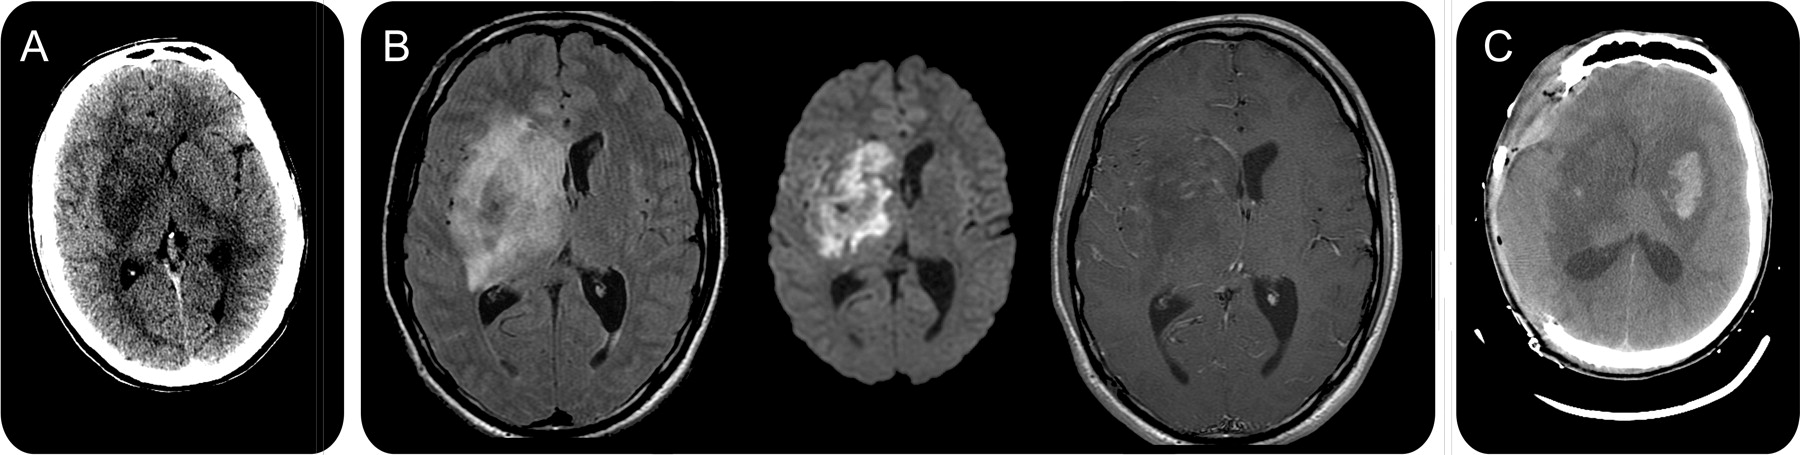

史的一个22岁的男人至少1年的静脉注射海洛因和可卡因滥用严重头痛和行走困难。他说症状出现后海洛因使用前一天。他被发现有发热、颈背的刚性,轻度左面部下垂,离开hemiataxia,轻微的脑病。血清的研究显示白细胞增多,消极的艾滋病毒测试,没有代谢紊乱,和消极的细菌培养。最初的头部CT显示一个大型低密度病变的基底神经节与温和的质量效应(图,一个),因此腰椎穿刺没有尝试。他是经验给予万古霉素,头孢曲松钠、甲硝哒唑无环鸟苷、磺胺甲恶唑/甲氧苄氨嘧啶。在接下来的24小时,病人开发左半身不遂和严重的脑病。MRI显示主要T2 hyperintense和T1 hypointense病变扩散限制,最小的增强,对基底神经节和不明确的利润(图、B)。梯度回波显示出血性组件。这些发现符合一个感染性或炎性大脑炎或局灶性缺血,血管炎的可能。出血性组件建议等真菌感染曲霉菌或毛霉菌spp第四,所以脂质体两性霉素B是补充道。他继续迅速恶化发展丧失理智的姿势和癫痫发作。病人插管,放在连续脑电图监测,给定的抗惊厥药物和脑室两性霉素b .重复CT证实的面积增大低衰减的基底神经节与质量效应的侧脑室和5.7毫米中线的转变。一个新的在左侧基底神经节病变瘀点也出现(图C),他接受了紧急正确hemicraniectomy预防腰椎间盘突出。由于高风险的立体定向活检更深层次的损伤,只有皮质活检是,它并没有发现病理变化。CSF演示-墨汁染色,革兰氏染色剂,和文化。隐球菌,组织胞浆菌属,曲霉属真菌,芽生菌病免疫血清学是负的。15天后没有改善,他的学生成为固定和扩张和CT显示病变的延伸到皮质和脑干。病人护理被撤回后死亡。他大脑的组织病理学尸检显示广泛的区域符合脓肿形成和球状薄壁真菌菌丝与90度的分支和罕见septations-all zygomycosis的暗示。

成像可能是最重要的线索孤立CNS zygomycosis的早期诊断。绝大多数的IVDA-related病例基底神经节的参与。1,6对比CT可以显示广泛的增强模式,只有少数病例报告与核磁共振。我们的案例也证明,一个重要特征是,单边基底神经节病变与低质量衰减迅速成为双边和更广泛,6强调了快速诊断和治疗的需要。